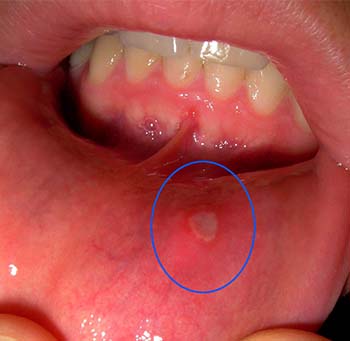

Mouth ulcers may occur inside the lips, inside the cheeks, gums, on tongue, below the tongue. they may occur anywhere in the mouth. they may be multiple or single in number and may come frequently.